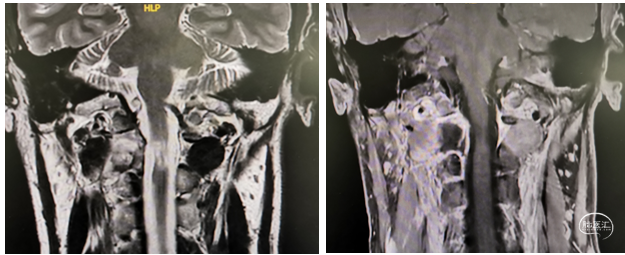

中山大学附属肿瘤医院影像医学中心的刘海彬医师为患者手术提供了高质量的影像学资料,为制定手术方案提供了很大的帮助。完善相关检查,经由神经外科脊髓脊柱亚专业组等MDT讨论,郭先生的C1-2椎管哑铃型硬膜内外沟通性占位行内镜下显微切除。全切肿瘤,避免损伤椎动脉、颈内外动脉及高位颈髓神经功能,维护脊柱的稳定性,是该手术的目标。张继教授阅片后提出:C1-C2椎管哑铃型硬膜内外沟通性肿瘤,考虑神经鞘瘤可能性大,后正中手术切口,通过体位调整结合患者的生理椎间隙扩大,可通过C1与C2椎板间隙入路,必要时磨除部分C2半椎板上沿,保留小关节囊,实现预定手术目标(对脊柱稳定性影响小,全切肿瘤)。

牟永告主任赞同该入路和肿瘤切除方案,采取化整为零的策略实现肿瘤全切。